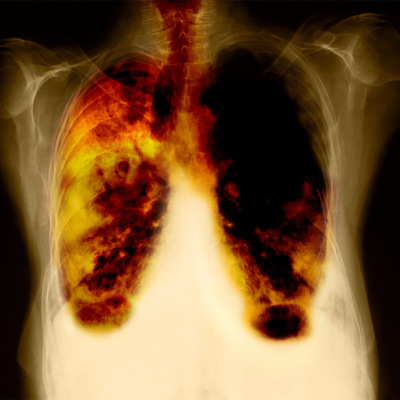

La mitad de las neoplasias de pulmón se detectan demasiado tarde - Los expertos debaten generalizar el cribado al igual que contra el tumor de mama y colon

Ahora bien, ¿qué ocurre con aquellas personas que durante su vida han sido grandes fumadores y aún siguen con riesgo de desarrollar una neoplasia? ¿Y las que continúan fumando? Muchos expertos coinciden en que si existiera un cribado de pulmón eficaz disminuiría la mortalidad del cáncer más letal -actualmente, a los cinco años de extirpar el tumor sólo sobrevive un 15%-. La mitad de los casos se diagnostican cuando ya no se puede operar.